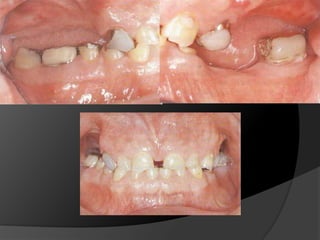

Diagnóstico y Planificación MultidisciplinariaEl examen clínico y la historia clínica nos darán información sobre los factores locales y sistémicos que pueden tener gran influencia en la obtención de un pronóstico para el tratamiento propuesto

Diagnóstico y Planificación MultidisciplinariaHistoria ClínicaAnamnesisFotografía clínica Montaje modelos de estudioEncerados DiagnósticosEvaluación Radiográfica Radiografías PeriapicalesRadiografía PanorámicaEvaluación DentalEvaluación PeriodontalEvaluación EndodónticaEvaluación OclusalEvaluación Articular?